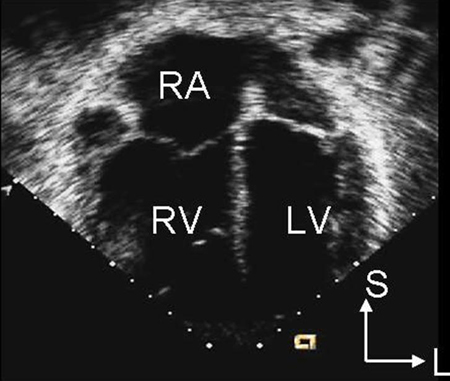

Imagem de ecocardiografia do eixo paraesternal curto revelando um aumento ventricular direito em um paciente com defeito do septo atrial (DSA). (VD) ventrículo direito; (VE) ventrículo esquerdo

Imagem cedida por Patrick W. O'Leary, MD